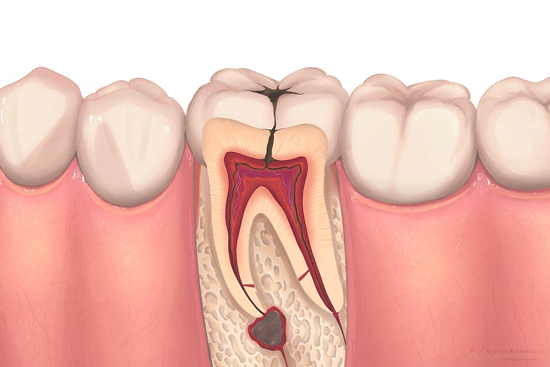

Understand Tooth Anatomy

Don’t lose a tooth to infection. Our painless root canal therapy removes the cause of pain while preserving your tooth’s structural integrity.

01

The Enamel

02

The Dentin

A sensitive, bone-like layer under the enamel that supports the tooth's structure and surrounds the pulp.

03

The Pulp

The living core of the tooth containing nerves and blood vessels. This is where root canals treat the infection.

Why Is It Needed?

Stopping the Infection

When the pulp is damaged, bacteria begin to multiply in the pulp chamber. Left untreated, this leads to an abscess—a pus-filled pocket at the end of the roots

Preventing Bone Loss

Severe infection can spread to the jawbone, causing bone loss around the root tips. This weakens the structural foundation of your entire dental arch.